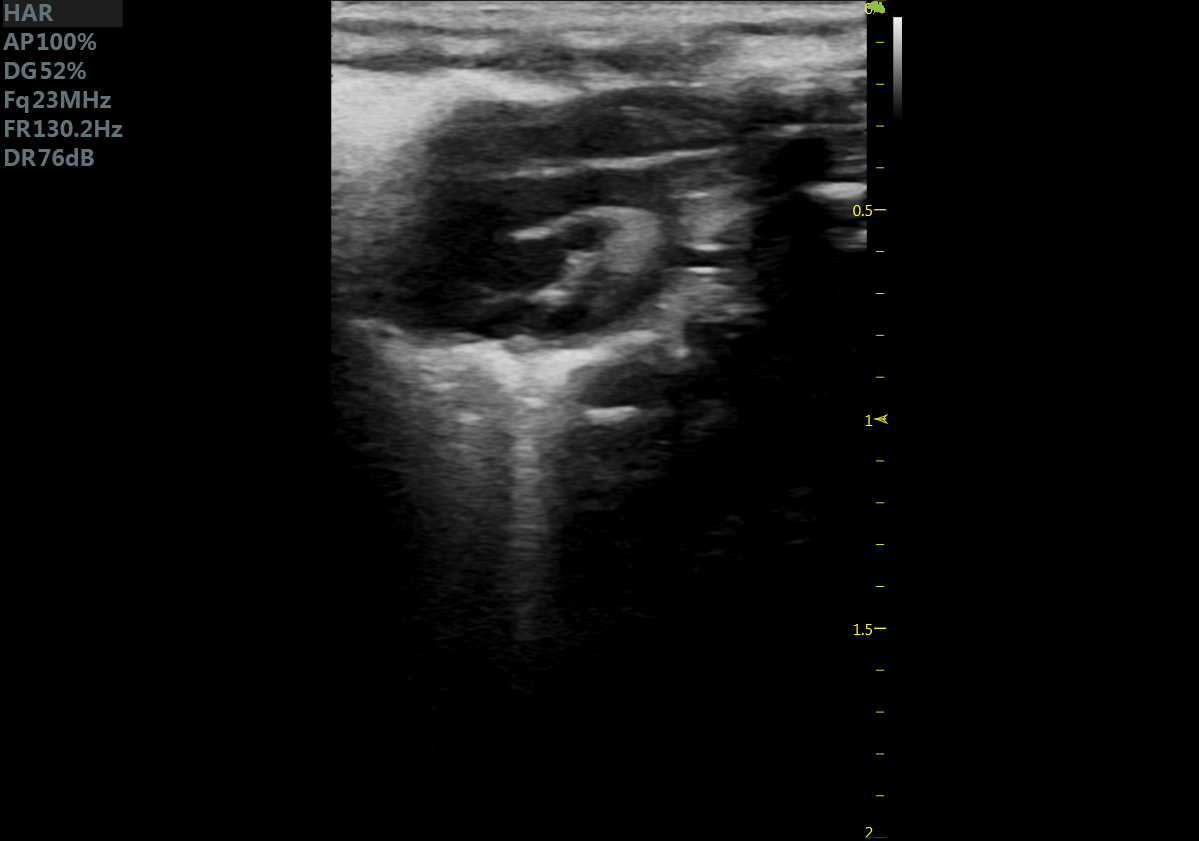

23MHz高频探头,优秀卓越的浅表显影

RF Flow充盈不外溢 Xcen超高频浅表显影

小鼠长轴M型 小鼠短轴M型

小鼠长轴B型 小鼠短轴B型

小鼠主动脉弓 小鼠肾脏血流

小鼠乳头肌水平 小鼠肝脏

大鼠短轴M型 大鼠长轴M型

大鼠长轴B型 大鼠主动脉弓

大鼠胎鼠心脏血流 大鼠心尖四腔

大鼠肝脏 大鼠肾脏